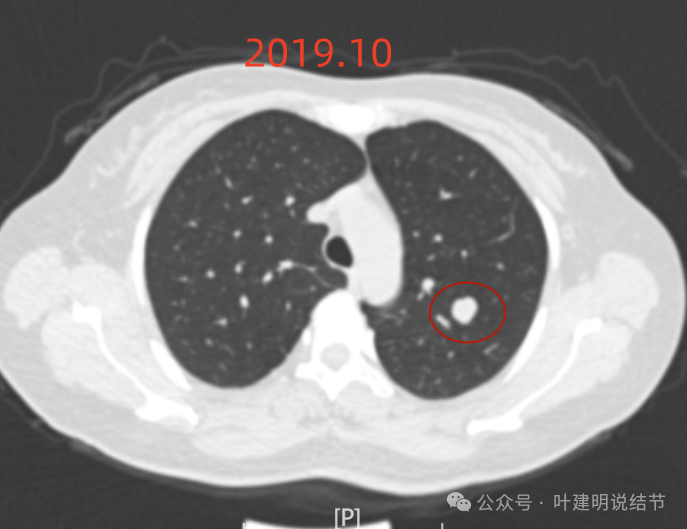

2019年10月,变化不大,但这个层面看略显得有膨胀感。